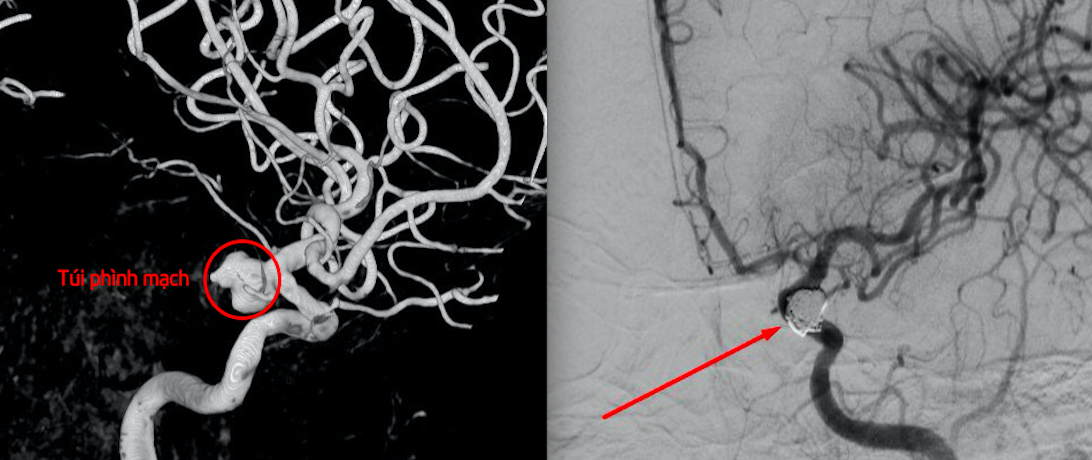

Kết quả chụp CT mạch não ở Bệnh viện Đa khoa Hùng Vương (Phú Thọ) cho hình ảnh chảy máu dưới nhện trong một số rãnh cuộn não bán cầu hai bên, rãnh Syvius hai bên, bể quanh cầu quanh cuống, tụ máu não thất bên hai bên do vỡ túi phình đoạn tận động mạch cảnh trong bên trái.

Can thiệp nút túi phình mạch não vỡ cho nữ bệnh nhân.

Thầy thuốc quyết định can thiệp nút túi phình mạch não vỡ bằng vòng xoắn kim loại Coil. Đây là kỹ thuật cao, chuyên sâu trong lĩnh vực can thiệp thần kinh, giúp mang lại cơ hội sống, hồi phục hoàn toàn cho nhiều trường hợp, dị dạng mạch não, vỡ phình mạch não nguy kịch.